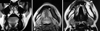

The T1-weighted MR images (T1WI) obtained using fat suppression (FS) showed a lesion with an iso-intense signal. Signal voids were not detected, suggesting a slow flow lesion. Internal loculations were noted in the coronal plane and the axial plane, suggesting multilocularity. The coronal T1WI (Fig. 5A) and the axial T1WI (Fig. 5B) showed an expansile low-intensity lesion in the marrow of the left hemi-mandible with a cortical break. The T2-weighted images (T2WI) showed hyperintense signals, thus confirming a vascular lesion (Fig. 5C). Axial T2WI showed high signal intensity and an expansile lesion in the marrow of the left hemi-mandible with a cortical break. MRI revealed the fluid-fluid levels in the aneurysmal bone cyst in T1WI, thus helping to differentiate it from vascular malformation. Further, Gd-T1WI showed heterogeneous signal intensity in the osteosarcoma, which was absent in vascular malformations. A slow flow malformation in the Gd-T1WI might sometimes present a "bubbly" appearance, which was seen in aneurysmal bone cyst (ABC) as well.5,6

A. A coronal T1 weighted MR image shows an expansile low intensity lesion in marrow of left hemi-mandible. B. An axial T1 weighted MR image shows low signal intensity expansile lesion in marrow of left hemi-mandible with cortical break. C. An axial T2 weighted MR image shows a high signal expansile lesion in marrow of left hemi-mandible with cortical break.